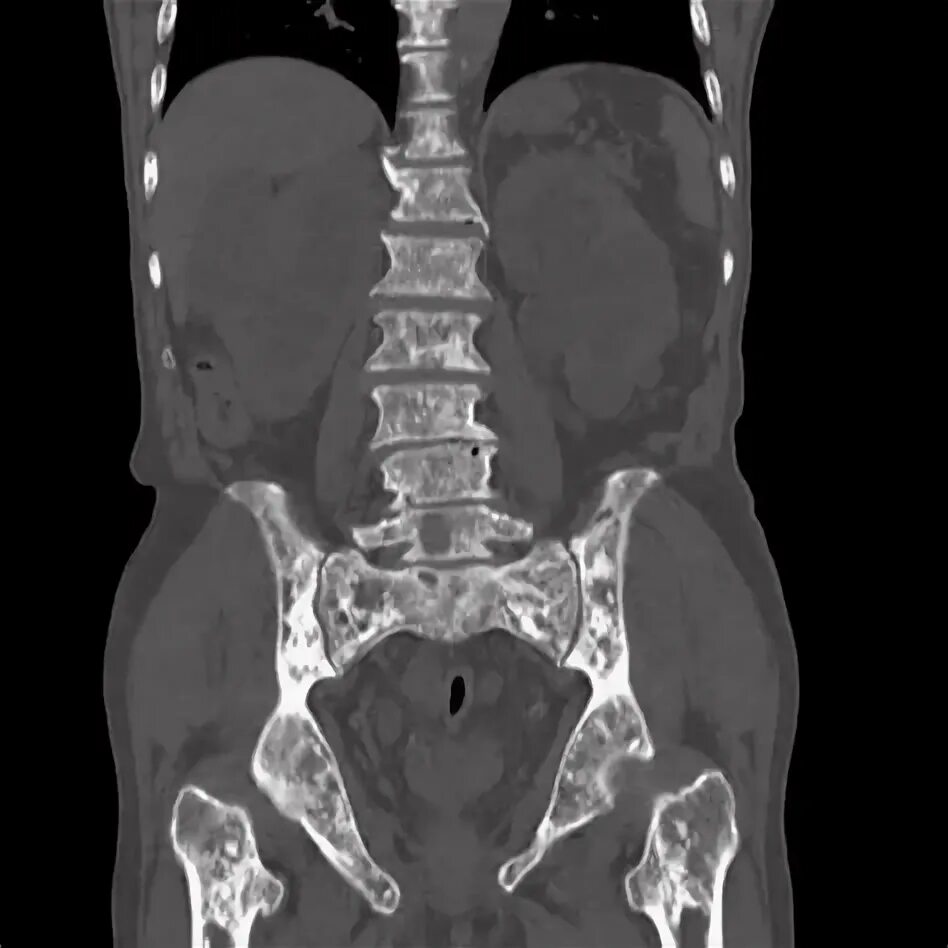

Метастазы в простате